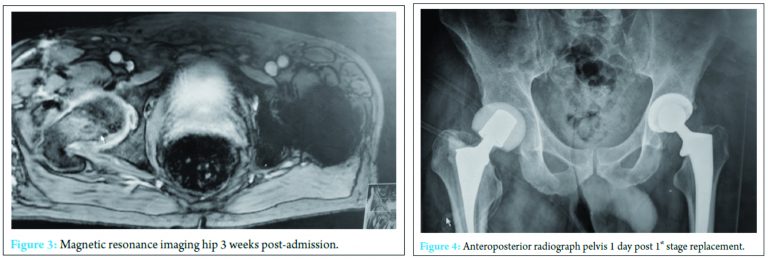

A 59-year-old physical education teacher with known right hip osteoarthritis was admitted with rapid onset of increasing right hip pain, inability to weight bear, pyrexia, and rigors. Relevant medical history included a successful left total hip arthroplasty, hemochromatosis, and hypercholesterolemia. There was no evidence of liver cirrhosis. Blood markers were elevated with a neutrophil leukocytosis of 24 × 103 cells/mm3 and C-reactive protein (CRP) of 514 mg/ml. Normal range 0-5 mg/ml (Fig. 1). Radiographs demonstrated right hip osteoarthritis while an ultrasound scan demonstrated a large echogenic right hip effusion with associated synovial thickening. The patient was managed with an urgent washout and debridement of his right hip joint through an anterior approach. Intraoperatively, intravenous teicoplanin 400 mg was commenced following collection of multiple fluid and tissue samples. A closed suction drain was left in situ that collected 200 ml of serosanguinous fluid in the first 24 h after which the drain was removed. Two pre-operative peripheral blood cultures and four separate fluid and tissue theater samples grew S. aureus, sensitive to flucloxacillin and sodium fusidate. Microbiology advised switching from intravenous teicoplanin 400 mg TID to intravenous flucloxacillin 2 g QDS and oral sodium fusidate 500 mg TID. He initially responded well with falling inflammatory markers, apyrexia, pain reduction, and a dry healing wound (Fig. 2).